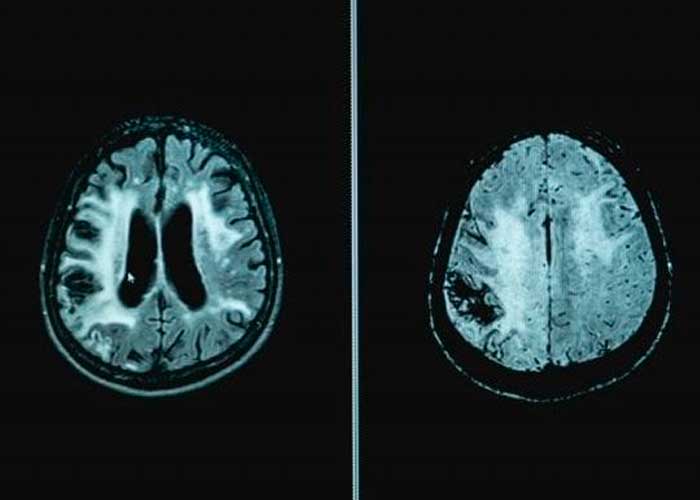

El equipo de investigación analizó escáneres cerebrales por resonancia magnética de más de 22.000 participantes del Biobanco del Reino Unido , buscando cambios en las vías de la materia gris y la materia blanca del cerebro, además de registrar los datos clínicos, demográficos y cognitivos de los voluntarios.

"El cerebro está formado por redes que conectan diferentes regiones y trabajan juntas para coordinar su pensamiento; estas regiones se comunican a través de vías de materia blanca", explicó Veldsman.